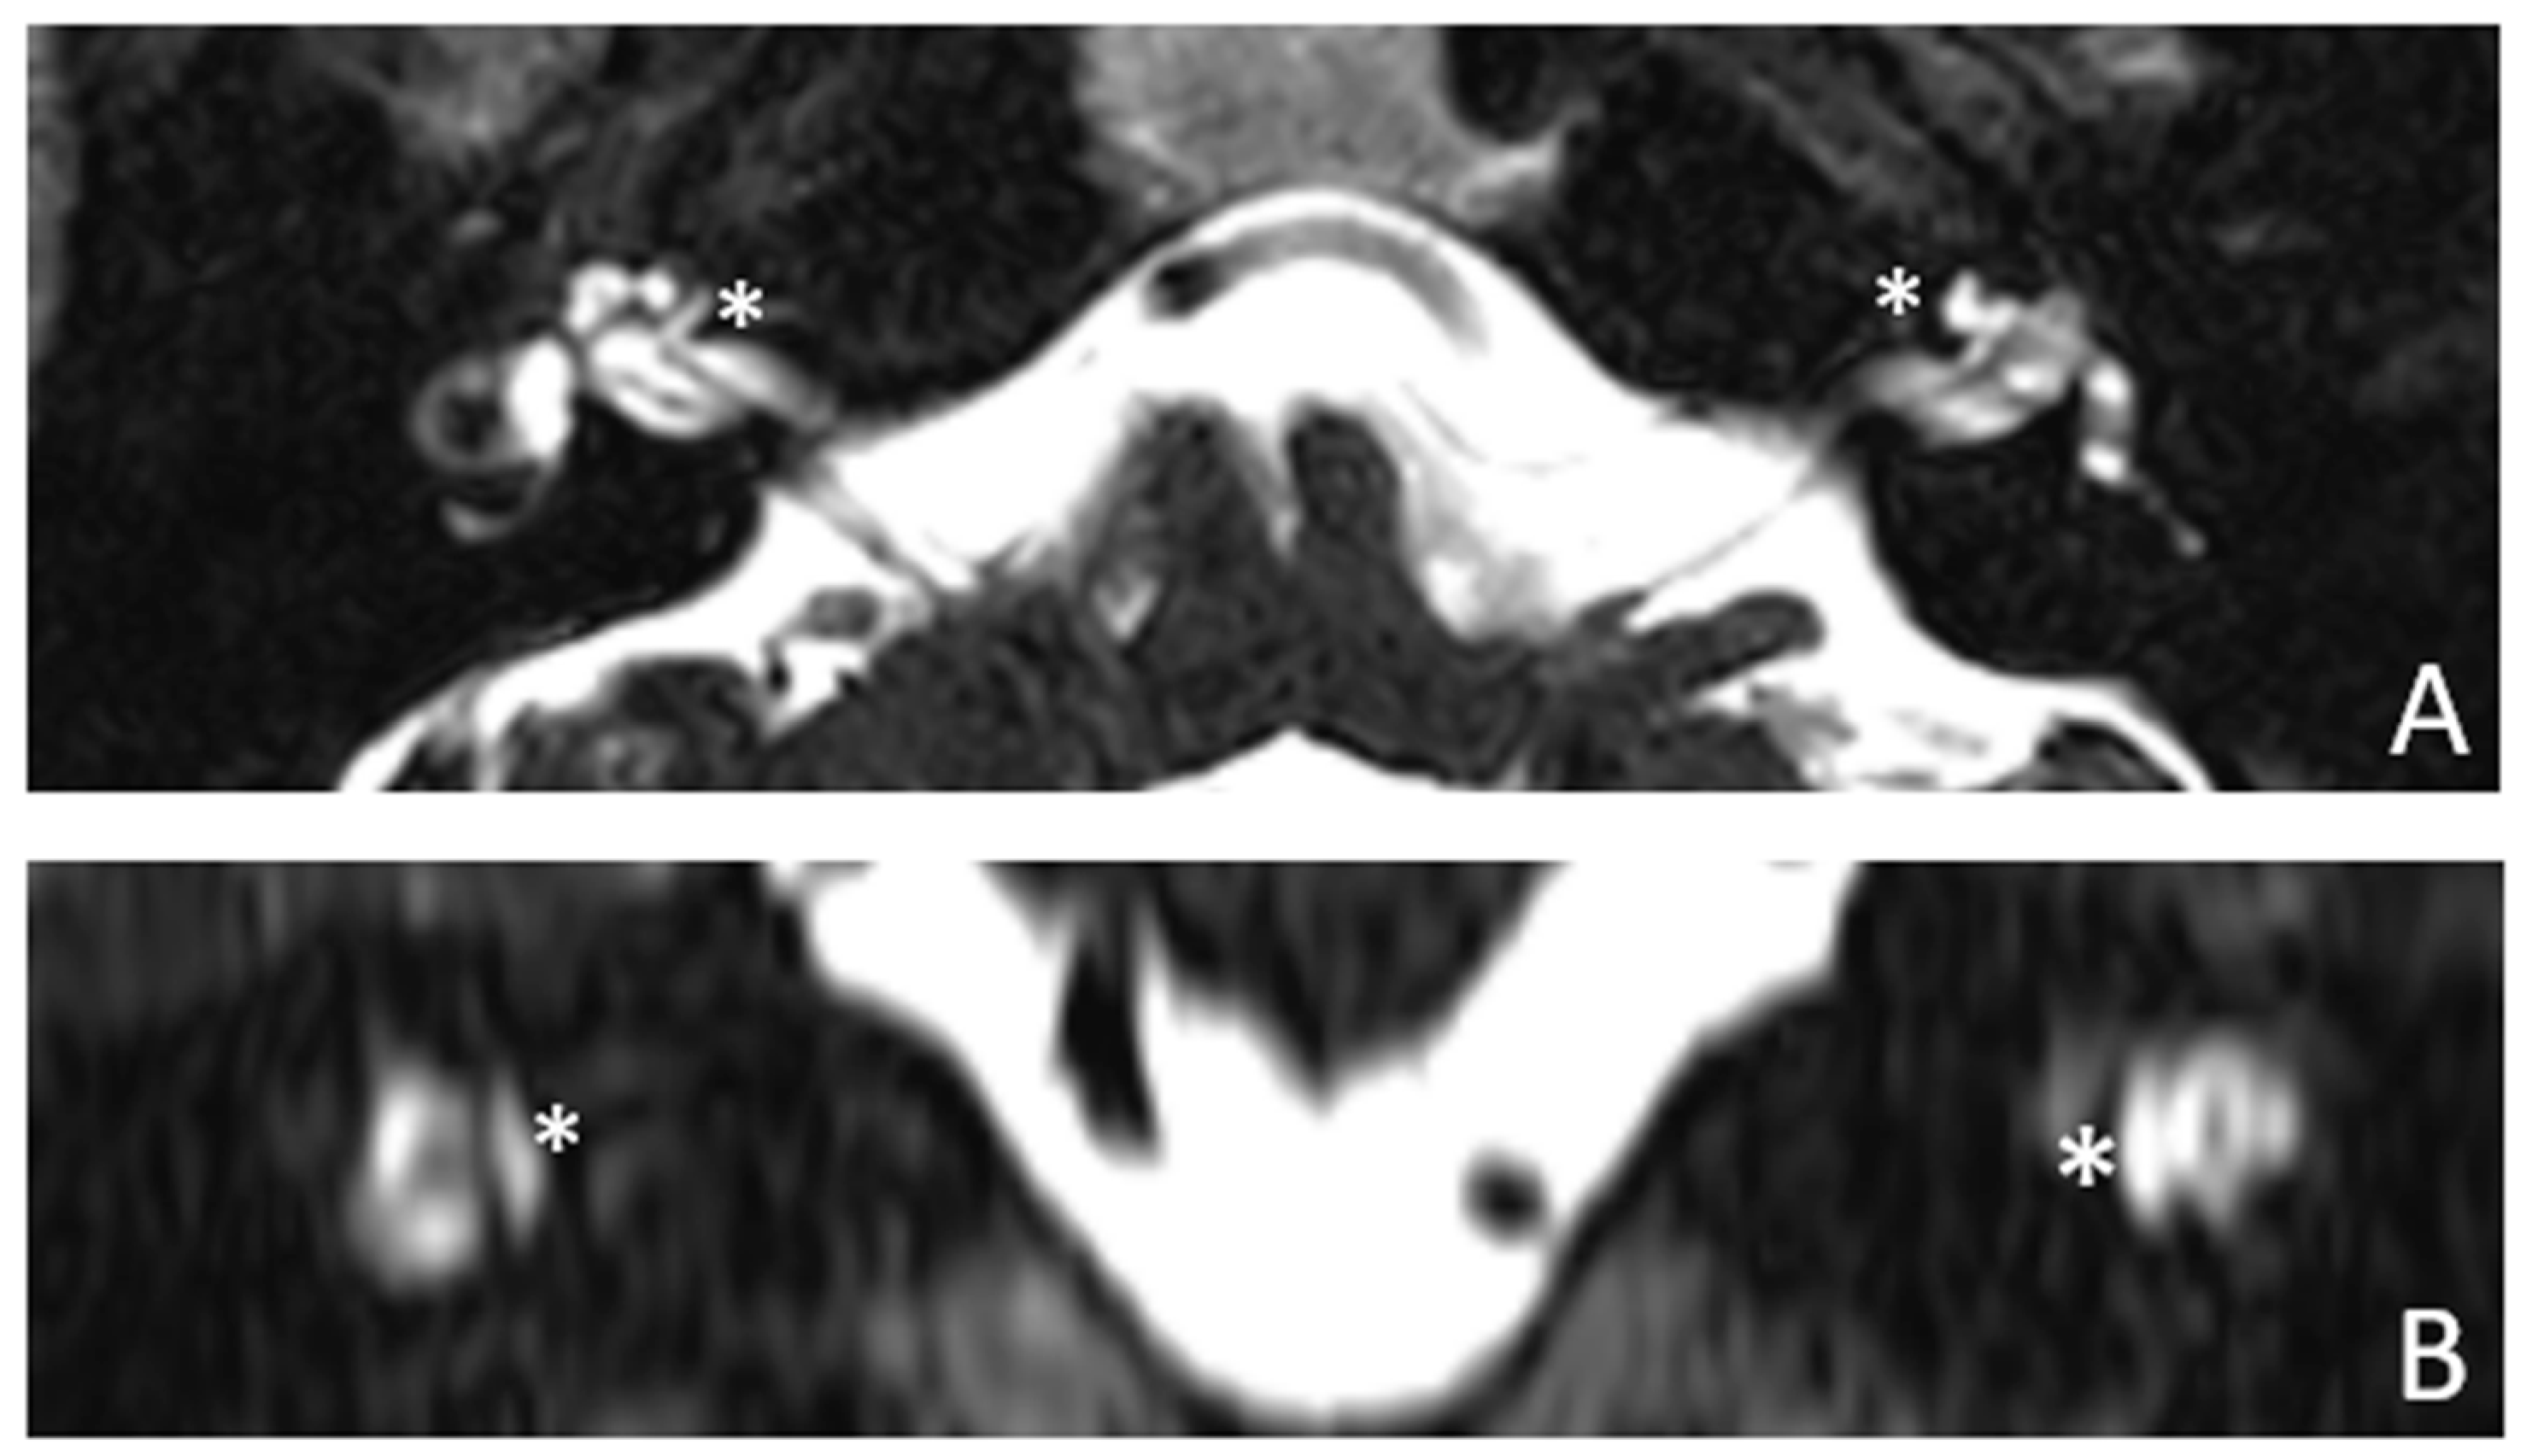

Within a few years, both ears showed progression of HL with worsening of bone threshold to SNHL bilaterally. In 2017 (27 years since diagnosis) she developed profound SNHL with left-sided anacusis and underwent cochlear implantation in the left ear. CT and MR images show a large cavity around the basal turn of the cochlea and massive osteorarefaction around the cochlea (‘double ring’ sign). The cavity appears to contain cerebrospinal fluid but does not communicate with the cochlear lumen (Figure 1 and Figure 2).

Figure 1. CT images of patient #1 with osteogenesis Imperfecta. A and B, right side in axial plane. C and D, right side in coronal plane. E and F, left side in axial plane. G and H, left side in coronal plane. A pericochlear cavity is visible in all figures;. arrows indicate its origin from the IAC. Asterisks indicate extension of osteorarefation into the cochlea.